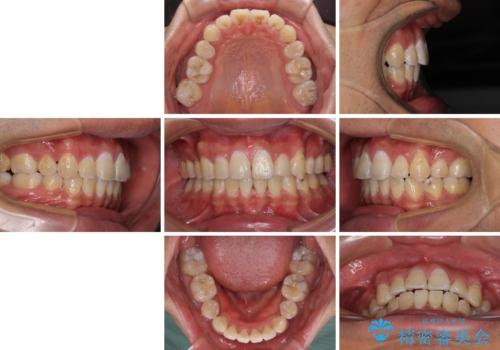

奥歯の咬み合わせを改善したいため、治療期間が長くなりましたが、患者様には辛抱強くお付き合いいただきました。

上下の正中を合わせることもでき、患者様には大変満足していただきました。